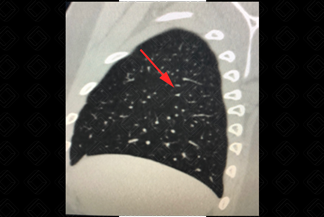

Texto alternativo para a imagem Figuras 1 e 2. Créditos: Dra. Elazir Mota - Rio de Janeiro/RJ

Descrição das figuras 1 e 2: Linfonodos intrapulmonares nas cissuras oblíquas direita e esquerda (setas vermelhas). [cms-watermark]

Algumas características tomográficas do tórax podem auxiliar no reconhecimento do linfonodo intrapulmonar:

• Esses linfonodos são ovais, redondos, triangulares ou trapezoidais, com bordas bem definidas;

• Localizam-se quase sempre abaixo do nível da carina, predominantemente nas regiões subpleurais dos lobos inferiores;

• Frequentemente estão aderidos à pleura ou separados da superfície pleural por alguns milímetros;

• Os linfonodos intrapulmonares têm aderências finas e lineares que se estendem do nódulo até a pleura (vide imagens).